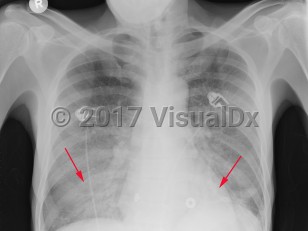

Pneumocystis jirovecii pneumonia

Typical onset in patients with HIV is insidious with a fever, dry cough, and progressive shortness of breath with exertion. There may be associated chest pain. Hemoptysis is not typical. Symptoms may progress for weeks or months before patients seek medical care.

The symptoms are typically more acute in onset and more severe in non-HIV-infected patients. These patients may present with respiratory failure.

Physical examination usually reveals fever, tachycardia, and tachypnea. Breath sounds are often normal, but in up to one-third of adults, rales are present. Impaired oxygenation is a common finding, particularly with ambulation, with varying degrees of hypoxemia and elevated alveolar-arterial (A-a) oxygen gradient.